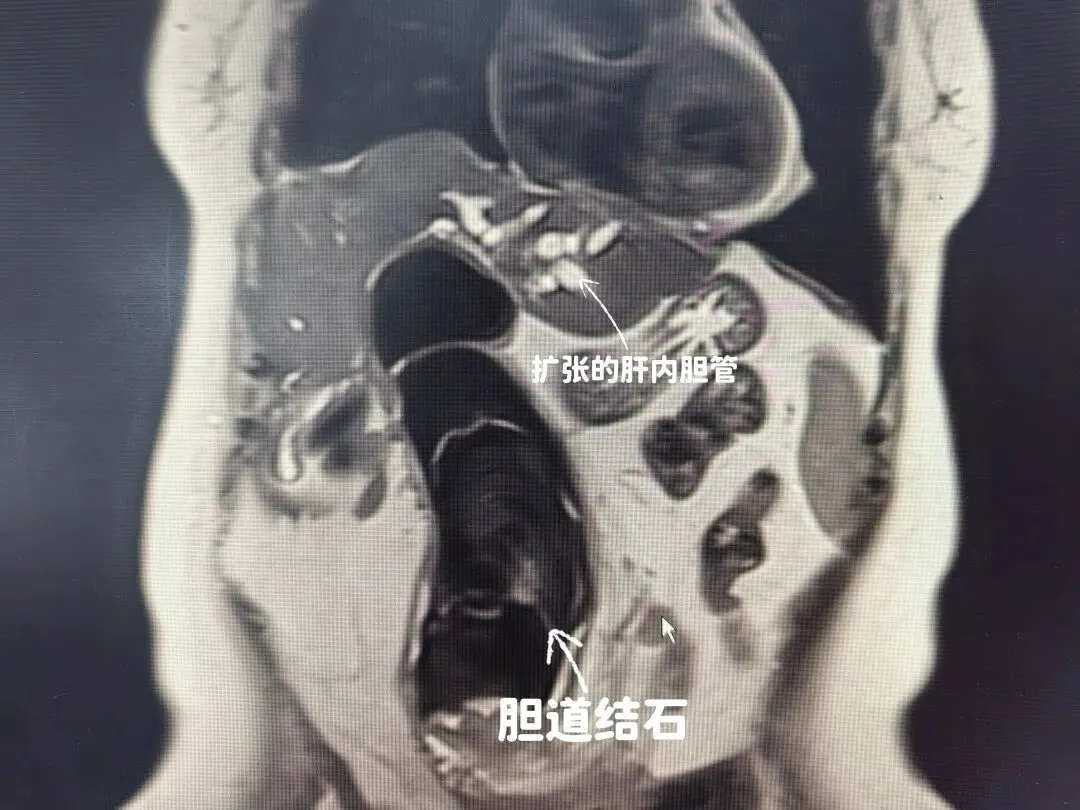

检查结果显示,在杨奶奶的腹腔里,竟然“藏”着一个惊人的大家伙——一颗长度达到20厘米的巨型结石。怎么形容呢?差不多有成人前臂那么长。它从肝内胆管里“长”出来,穿过早年手术搭建的“通道”(胆管空肠吻合口),一路“钻”到了空肠的深处。这还不算完,肝内和胆总管里,还有不少“小石头”散落着。